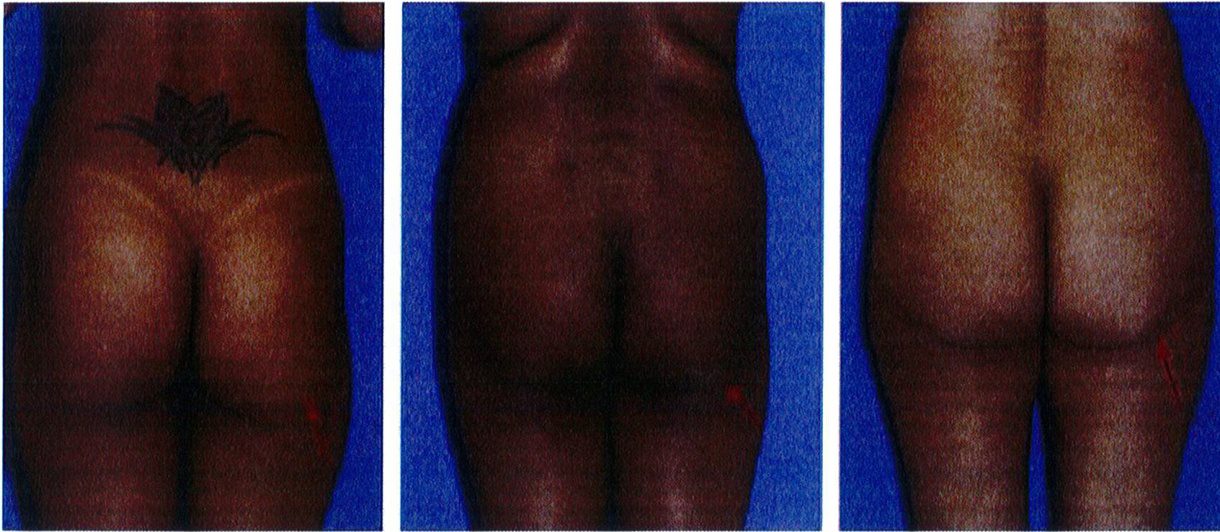

Khung vuông là phổ biến nhất, gặp ở khoảng 40% số bệnh nhân. Vị trí A và B tương tự nhau, đặc trưng cho phần mông hình vuông để khi các điểm này nối với nhau sẽ được một hình vuông (Hình 7 và 8). Điểm C có thể có các mức độ lõm (thiếu mô mỡ) khác nhau. Đây là dạng khung dễ chỉnh hình nhất trong cả 4 kiểu khung vì bất kỳ sự thay đối nào ở 1 trong 3 điểm A,B,C đều có thể biến khung này thành dạng khung khác.

Dạng còn lại là dạng trung gian, nằm giữa dạng khung cao và khung thấp vừa mới đề cập ở trên. Cơ mông lớn có chiều cao/rộng = 1:1 hoặc 2:1. Mông dạng vuông thường được cải thiện tương đối nhiều khi hút mỡ điểm A và B. Điểm C có thể cần ghép mỡ, tùy thuộc vào mức độ lõm tại điểm này (Hình 9).

Hình dạng này độc đáo ở chỗ chúng có thể cao, trung bình hoặc ngắn (Hình 7 và 8). Để hiểu rõ khái niệm này, cần phải nhớ rằng khung bao gồm da, mỡ và xương. Khung xương chỉ hữu ích để xác định đây là khung cao, trung bình hay ngắn. Giới hạn trên của khung xương là đường viền trên của mào chậu. Nên tùy thuộc độ cao của chúng mà cơ mông lớn sẽ bám vào khung xương tại các vị trí khác nhau. Cụ thể, biến thể đầu tiên gắn đường viền trên cơ mông lớn dọc Theo đường viền trên của toàn bộ mào chậu, chúng để lại rất ít khoảng trống giữa bờ trên của cơ và mào chậu. Loại này hình thành khung chậu ngắn, tỉ lệ cao/rộng của khối cơ là 1:1. Dạng biến thể thứ hai, cơ bám thấp hơn trên khung chậu, sao cho mép trên của cơ cách mào chậu khoảng ½ chiều dài cơ. Loại này được gọi là khung chậu cao, cơ thường có tỉ lệ cao/rộng là 2:1 (Hình 8)

Dạng tròn gặp ở khoảng 15% số bệnh nhân. Dạng này có đặc điểm là xuất hiện lượng mỡ thừa ở điểm C. Khi cả 3 điểm (A, B và C) được kết nối với nhau, một đường cong hình chữ C sẽ được hình thành (Hình 10). Điểm C rất quan trọng vì nó giúp phân biệt khung tròn với khung vuông. Khi điểm C lõm dần, khung từ dạng tròn chuyển dạng vuông.

Khoảng 15% số bệnh nhân có dạng khung hình chữ V. Khi nối điểm A và B với nhau, có thể thấy chúng hội tụ lại 1 điểm ở dưới mông, tạo hình chữ V. Hầu hết mô mỡ nằm ở vùng mặt ngoài hông (điểm A) và rất ít ở điểm B. Ở dạng này, tình trạng lõm ở điểm C không quá đáng ngại. Khi điểm A nhỏ đi, mông sẽ có khung vuông.

Khung chữ A gặp ở khoảng 30% bệnh nhân. Khi nối các điểm A và B, tạo ra hình dạng gần như chữ A (Hình 11). Hình dạng này đặc biệt vì chúng tích nhiều mỡ ở hơn ở vùng đùi ngoài phía trên (điểm B) và ít chất béo hơn ở vùng hông bên (điểm A). Lý tưởng nhất là điểm A nhô ra nhiều hơn một chút. Lúc này, khi rút chất béo ở điểm B đi, mông bắt đầu có dạng vuông. Điểm C có thể bị lõm đi nhiều, song ở dạng này hầu hết các trường hợp chỉ lõm mức nhẹ hoặc trung bình.

Khung chữ A gặp ở khoảng 30% bệnh nhân. Khi nối các điểm A và B, tạo ra hình dạng gần như chữ A (Hình 11). Hình dạng này đặc biệt vì chúng tích nhiều mỡ ở hơn ở vùng đùi ngoài phía trên (điểm B) và ít chất béo hơn ở vùng hông bên (điểm A). Lý tưởng nhất là điểm A nhô ra nhiều hơn một chút. Lúc này, khi rút chất béo ở điểm B đi, mông bắt đầu có dạng vuông. Điểm C có thể bị lõm đi nhiều, song ở dạng này hầu hết các trường hợp chỉ lõm mức nhẹ hoặc trung bình. Dạng khung này thường được cải thiện khi hút mỡ ở điểm B hoặc vùng đùi bên (Hình 12). Điểm C có thể cần ghép mô mỡ, tùy thuộc vào mức độ lõm. Nên tránh hút mỡ quá nhiều ở điểm B để ngăn chặn điểm lõm ở khu vực này, ngẫu nhiên hình thành ranh giới giữa vùng mông và mặt ngoài đùi.

Hình. 9. Minh họa khung vuông, cao trước (trái) và sau (phải) phầu thuật chỉnh hình mông.

Hình. 11. Hình minh họa khung dạng chữ A với mức độ lõm nhẹ, trung bình và nhiều ở điểm C. Điểm A nên là điểm lồi ra nhiều nhất của vùng mông ở dạng này, nên sẽ thực hiện hút mỡ ở điểm B để cân đối lai.

Hình. 12. Khung mông dạng chữ A, cao trước (bên trái) và sau (bên phải) nâng mông thẩm mỹ.

Hình. 15. Khung hình chữ V, cao với khối cơ mông lớn ngắn trước (trái) và sau (phải) phẫu thuật tạo hình.